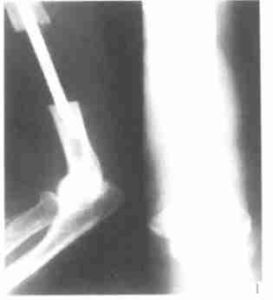

3.X線攝片可見軟組織腫塊,腫瘤內有不規則鈣化,骨質可有破壞,骨膜反應少。

1.X線表現約30%的病變中可以見到模糊散在的鈣化,有時可見骨膜反應,甚至侵蝕骨或侵入骨內。開始僅表現為軟組織腫塊,以後腫塊內可出現鈣化。對於病變內有點狀鈣化者應考慮與軟骨瘤或血管瘤相鑑別。2.骨掃描在掃描的晚期,可見病變內礦化活躍區的周圍有局限的攝取量增加(圖5)。由於病變的新生血管豐富,在掃描的早期可見病變區攝取量高於鄰近軟組織。